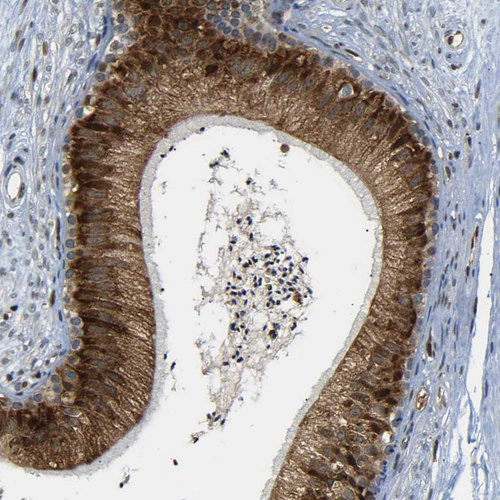

Immunohistochemical staining of human Epididymis shows strong cytoplasmic positivity in glandular cells.